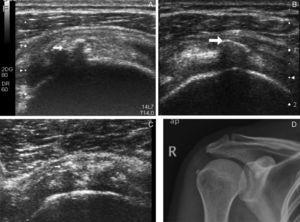

Debe diferenciarse de la tendinopatía por depósito, principalmente de hidroxiapatita (y menos frecuentemente, de urato monosódico o de pirofosfato cálcico)3 en la que el depósito de cristales es intratendinoso pudiendo producir rotura del suelo del tendón, y extenderse al interior de la bolsa subacromial (fig. 3).

Artropatía por depósito de hidroxiapatita. (a) Calcificaciones intratendinosas (ver flecha). (b) Calcificación en suelo de bolsa subacromial. (c) Pequeñas calcificaciones en porción anterior del SE y una de ellas (ver flecha) en el interior de bolsa subacromial). (d) Calcificación tendinosas del supraespinoso en radiografía simple.